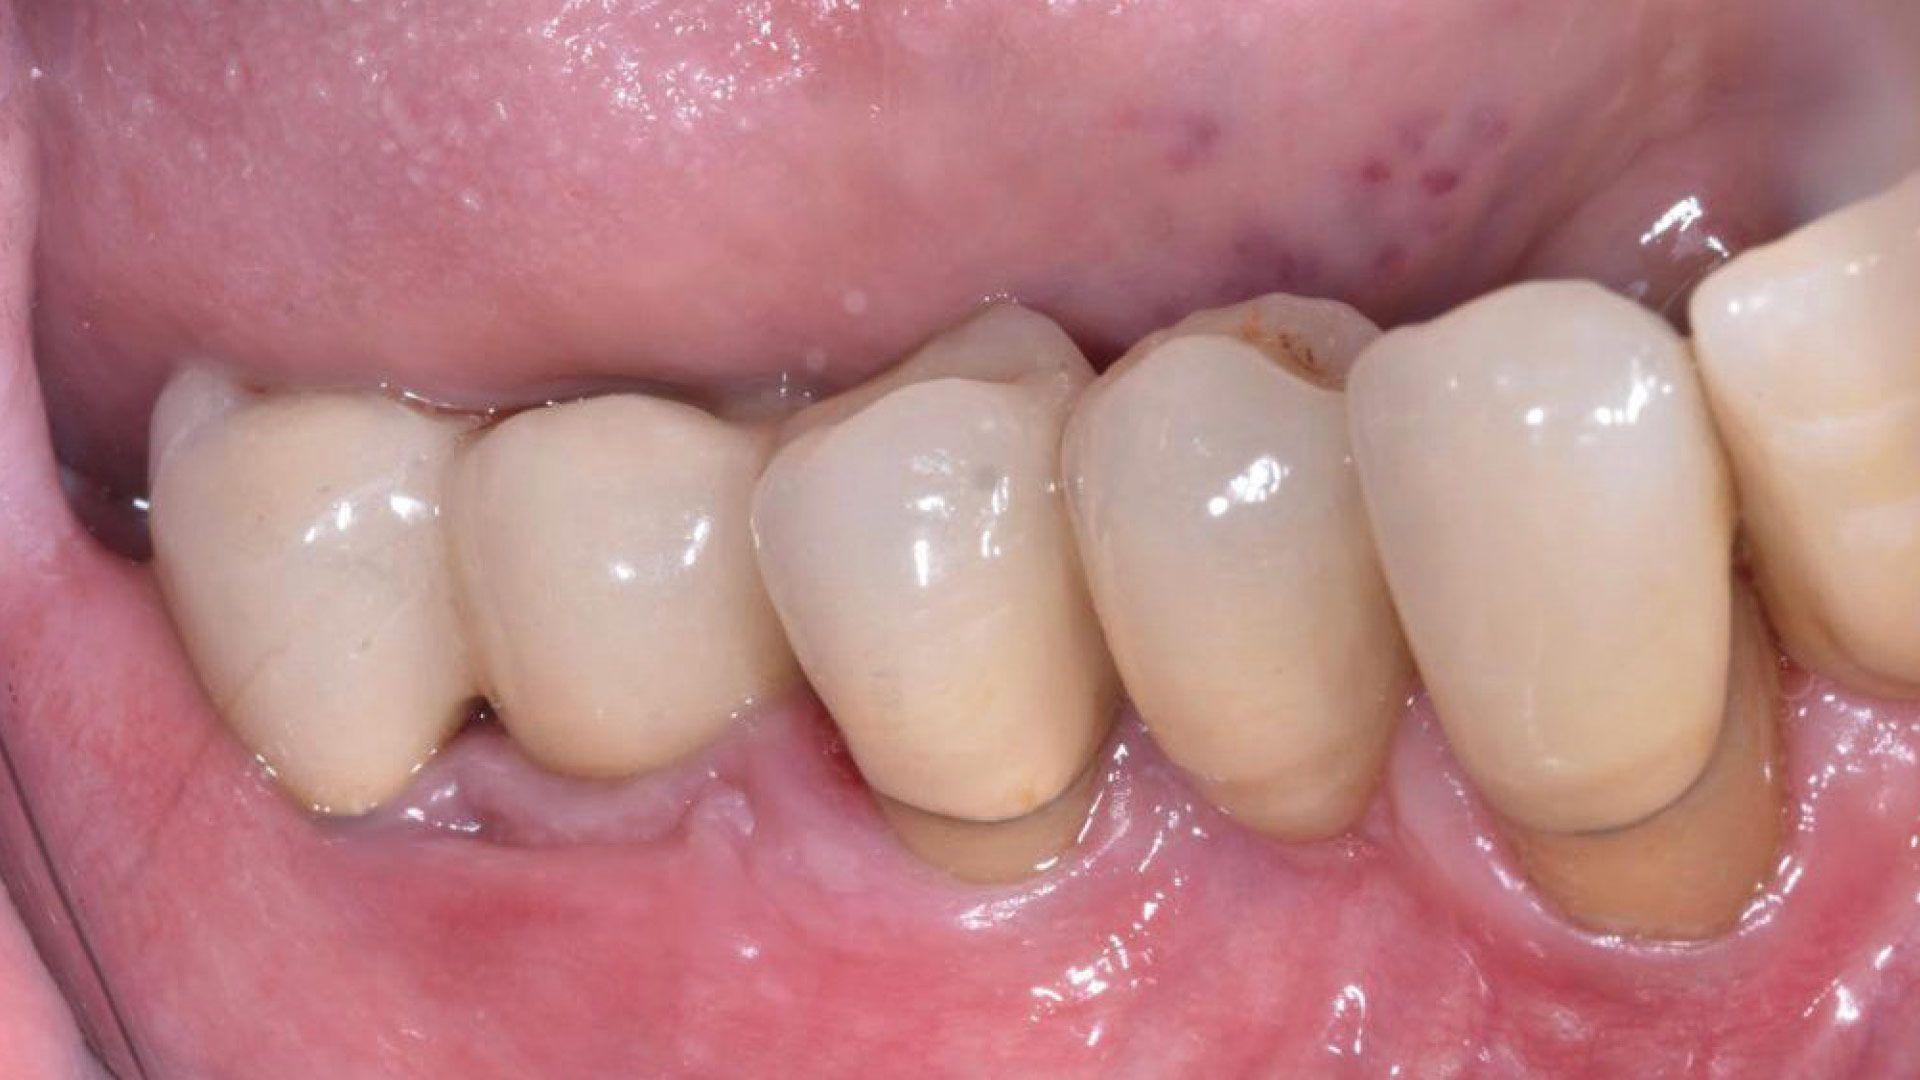

Lo studio è stato condotto presso studi dentistici privati con sede a Roma e Como. Sono stati reclutati 27 pazienti e divisi in gruppo 1 (applicazione di gel a base di clorexidina nei siti con mucosite perimplantare), gruppo 2 (applicazione di gel a base di Ozono) e gruppo 3 controllo (senza utilizzo di gel topici). Al baseline (T0) si è proceduto a valutare lo stato clinico dell’elemento implantare attraverso foto e radiografie periapicali, è stato poi rilevato l’indice di sanguinamento (Gengival Index) e successivamente è stato eseguito un debridement sub-gengivale tramite l’utilizzo di Glicina. Per il trattamento domiciliare ai pazienti sono stati consegnati gel a base di Ozono o di Clorexidina al 1% da applicare nei siti tramite lo scovolino. A T1(a 1 mese da T0) e a T2 (a 3 mesi da T0) sono state ripetute le stesse valutazioni e le stesse manovre professionali (Figg. 1a-6).

Figg. 1a, 1b - Gruppo 1: elemento 46, immagine acquisita a T0; Fig. 2 - Gruppo 1: elemento 46, immagine acquisita a T1; Fig. 3 - Gruppo 1: elemento 46, immagine acquisita a T2; Figg. 4a, 4b - Gruppo 2: elemento 11, immagine acquisita in T0; Fig. 5 - Gruppo 1: elemento 11, immagine acquisita in T1; Fig. 6 - Gruppo 2: elemento 11, immagine acquisita in T2.